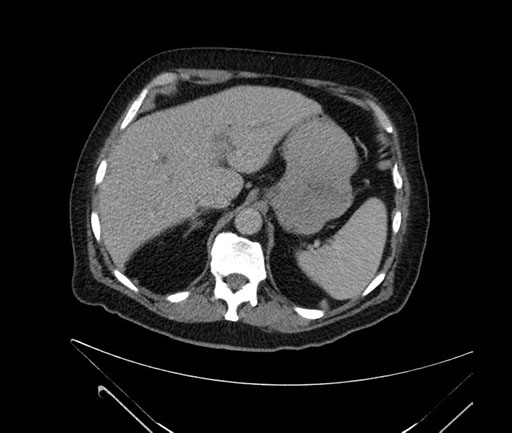

Imaging Analysis

Look through the patient's CT scan to identify any areas of concern for the necessary procedure.

Based on your CT findings, which issue(s) would give reason for "planned slowing down moment(s)" in this case?